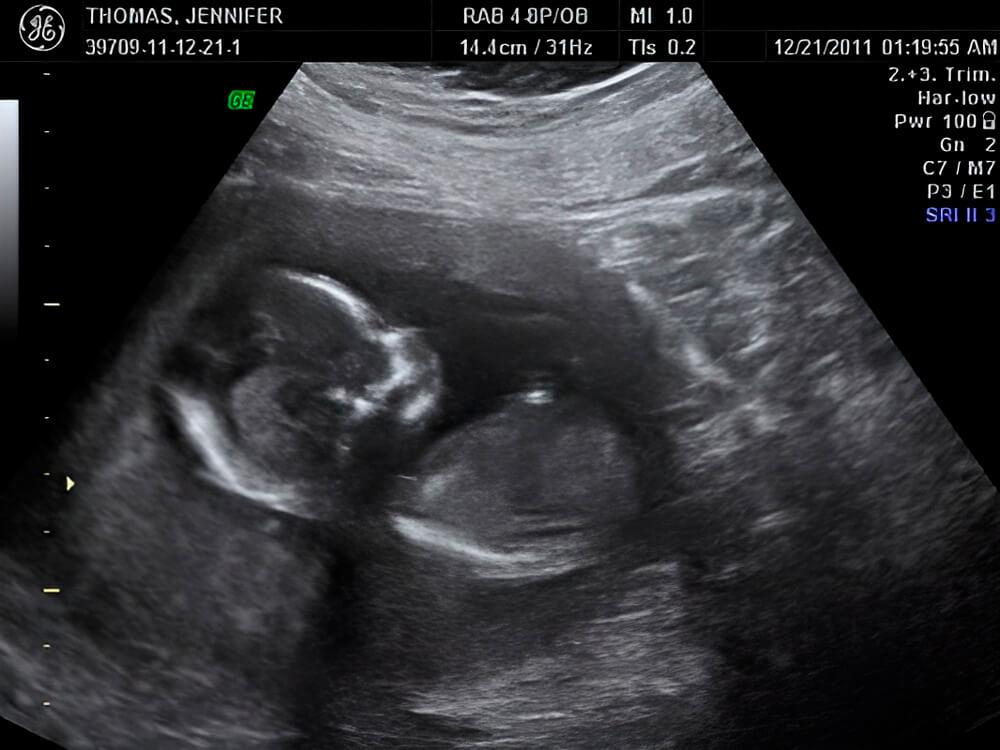

¡Tu bebé ya puede escucharte!

Tu bebé ahora puede escuchar sus primeros sonidos, como el latido de su corazón; pero aún no escucha los sonidos del mundo que lo rodea [1]. Todo su oído se formará por completo entre las 22 y las 24 semanas.

El cerebro se está desarrollando con intensidad en esta semana. Los hemisferios izquierdo y derecho están cubiertos de surcos y pliegues, y el proceso de división de las células nerviosas comienza esta semana.

Los brazos y las piernas del bebé continúan creciendo y aparecen uñas en sus dedos. El tejido graso subcutáneo aún no se ha desarrollado, por lo que los vasos sanguíneos brillan a través de las capas de la piel, haciendo que el bebé se vea rojizo.

¡En esta semana al bebé también le comienza a crecer su cabello! Pronto el color del mismo estará determinado por los genes del bebé y las células responsables del color comenzarán a producir un tinte.

El desarrollo de la médula ósea continúa y los órganos internos comienzan a funcionar. El intestino se llena de manera gradual con meconio, nombre que se le da a la primera evacuación del bebé que, por cierto, es de color negro verdoso debido a que contiene bilis.

Para el desarrollo y el crecimiento, su bebé necesita un mayor suministro de sangre y de tantos nutrientes como sea posible. La carga en la placenta aumenta, y crece hasta un poco más de media pulgada (17.7 mm) de espesor.